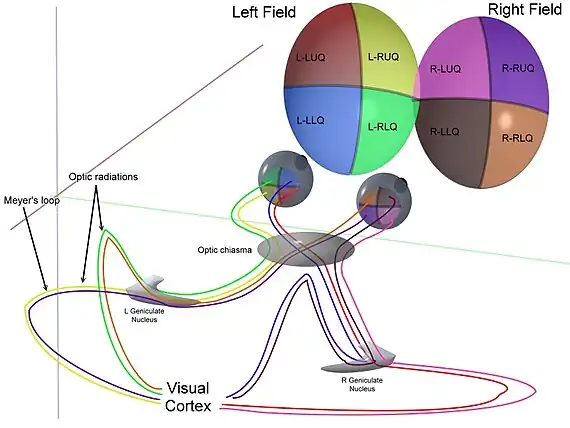

Colour-coded diagram showing radiations in quadrants from retinal disc through the brain | |

In neuroanatomy, the optic radiation (also known as the geniculocalcarine tract, the geniculostriate pathway, and posterior thalamic radiation) are axons from the neurons in the lateral geniculate nucleus to the primary visual cortex. The optic radiation receives blood through deep branches of the middle cerebral artery and posterior cerebral artery.

They carry visual information through two divisions (called upper and lower division) to the visual cortex (also called striate cortex) along the calcarine fissure. There is one set of upper and lower divisions on each side of the brain. If a lesion only exists in one unilateral division of the optic radiation, the consequence is called quadrantanopia, which implies that only the respective superior or inferior quadrant of the visual field is affected. If both divisions on one side of the brain are affected, the result is a contralateral homonymous hemianopsia.

The upper division:

- Projects to the upper bank of the calcarine fissure, called the cuneus

- Contains input from the superior retinal quadrants, which represents the inferior visual field quadrants

- Transection causes contralateral lower quadrantanopia

- Lesions that involve both cunei cause a lower altitudinal hemianopia (altitudinopia)

The lower division:

- Loops from the lateral geniculate body anteriorly (Meyer's loop), then posteriorly, to terminate in the lower bank of the calcarine sulcus, called the lingual gyrus

- Contains input from the inferior retinal quadrants, which represents the superior visual field quadrants

- Transection causes contralateral upper quadrantanopia

- Transection of both lingual gyri causes an upper altitudinal hemianopia

A distinctive feature of the optic radiations is that they split into two parts on each side:

| Source | Path | Information | Damage |

|---|---|---|---|

| Fibers from the inferior retina (also called "Meyer's loop" or "Archambault's loop") | must pass through the temporal lobe by looping around the inferior horn of the lateral ventricle. | Carry information from the Superior part of the visual field | A lesion in the temporal lobe that results in damage to Meyer's loop causes a characteristic loss of vision in a superior quadrant (quadrantanopia or "pie in the sky" defect.) |

| Fibers from the superior retina* | travel straight back through the parietal lobe to the occipital lobe in the retrolenticular limb of the internal capsule to the visual cortex. | Carry information from the Inferior part of the visual field | Taking the shorter path, these fibers are less susceptible to damage. Damage caused is characteristically called "Pie in the floor" defect or inferior quadrantanopia. |